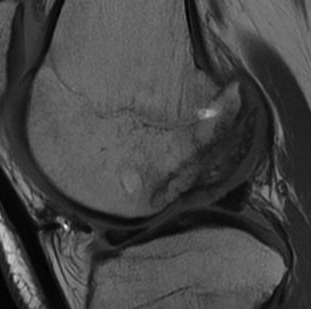

- MRI cartilage sequences at 3 and 6 months to assess cartilage healing